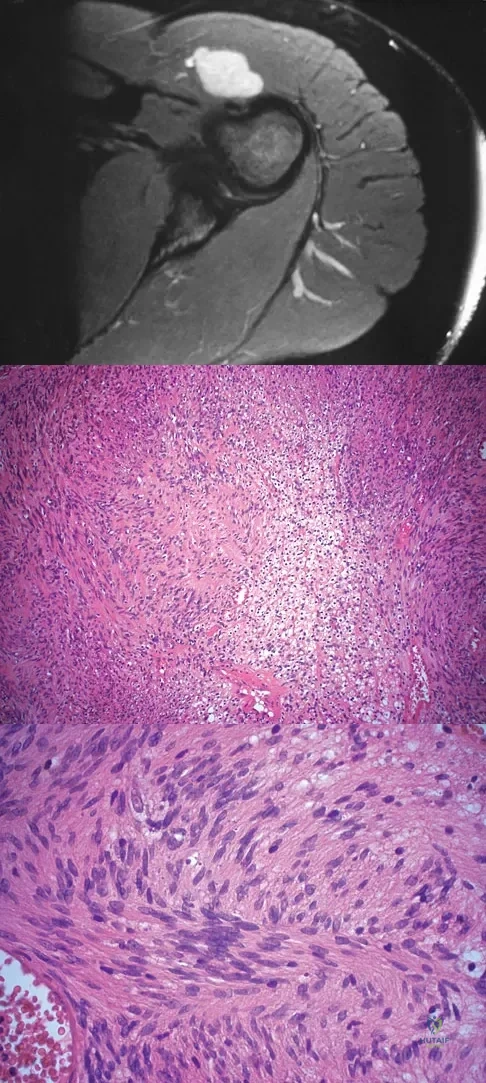

A coronal MRI scan through the shoulder joint is shown in Figure 26. The cyst indicated by the arrow will most likely cause compression of what nerve?

Explanation

A 10-year-old boy has a painful thigh mass. A radiograph, MRI scan, and biopsy specimen are shown in Figures 42a through 42c. What is the most likely diagnosis?

Explanation